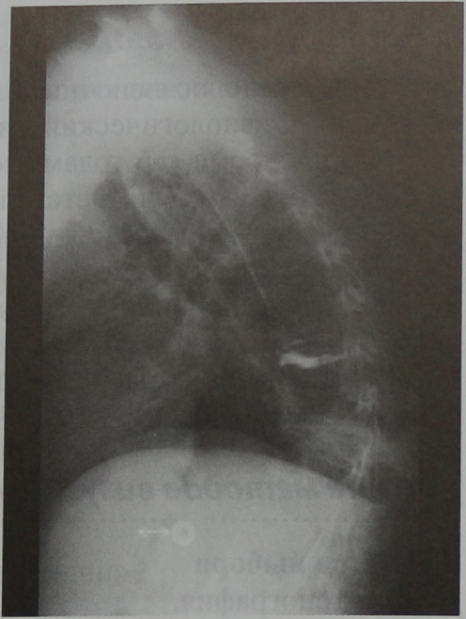

Мужчина 74 лет с анкилозирующим спондилитом и растущим горбом, состояние после вертебропластики. Рентгенограмма грудного отдела позвоночника на уровне позвонка Th9, боковая проекция. Обызвествление продольных связок, слегка бочкообразная форма тел позвонков и прогрессирующий кифоз грудного отдела позвоночника.

Женщина 74 лет с горбом и остеопорозом. Рентгенограмма грудного отдела позвоночника, боковая проекция. Уменьшение высоты позвонков в средней части грудного отдела, особенно спереди, что привело к развитию прогрессирующего кифоза (кифоз вследствие остеопороза).

Женщина 60 лет с остеопорозом, контрольная рентгенограмма (через 1 год) по поводу бронхиальной астмы. Боковая проекция. Патологический кифоз грудного отдела позвоночника с компрессионным остеопоротическим переломом позвонка в среднегрудном отделе позвоночника (кифоз вследствие остеопороза).